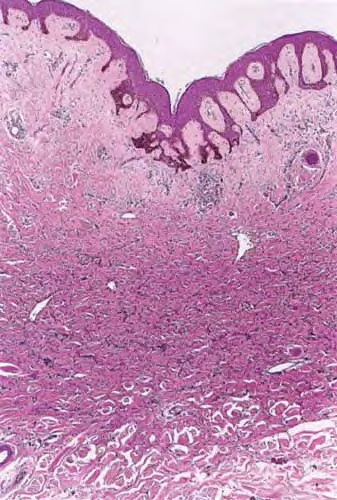

The overlying epidermis is usually acanthotic. Pseudoepitheliomatous hyperplasia and a basaloid proliferation may be noted. The hyperplasia may be caused by the action of fibroblasts on epidermal keratinocytes.23  Basal cell carcinomas occurring upon a dermatofibroma have been reported. Increased pigment may be seen, which may be iron or melanin. Most lesions display a grenz zone of normal papillary dermis overlying the tumor.

The bulk of the tumor is within the mid dermis where no capsule is present and the periphery of the lesion blends with the surrounding tissue. Whorling fascicles of a spindle cell proliferation with excessive collagen deposition are characteristic. At the periphery, the spindle cells characteristically wrap around normal collagen bundles (see the images below). Occasionally, melanocytes have been reported to be interspersed amongst the spindle cells.24